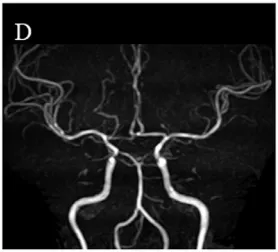

但是这位女性头部除了不规则的颅内动脉壁,MRI没有烟雾病的证据(图1,D),也从未经历过短暂的和长期性的神经系统症状。

烟雾病患者脑血管造影图像